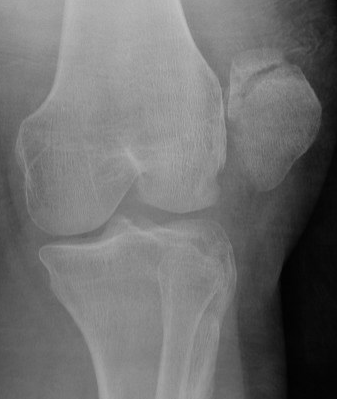

Xray

Look for osteochondral fractures

- skyline xray: suprapatella pouch

Osteochondral fracture visible on skyline view

Large medial patella osteochondral fracture

Large lateral femoral condyle osteochondral fracture